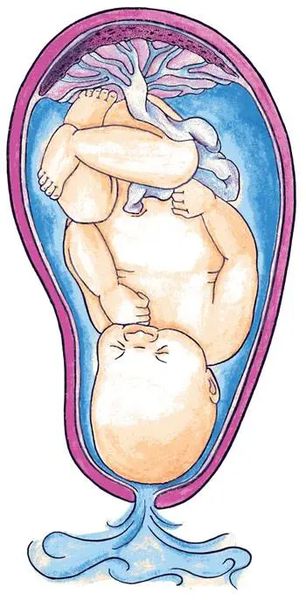

Медицинские аспекты мекония в околоплодных водах